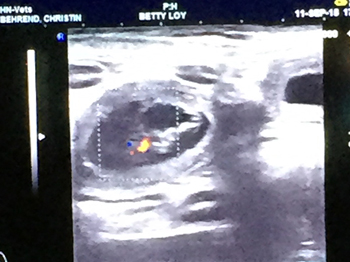

Heute, am

11.September waren wir beim Ultraschall,

und wir haben richtig geraten....

jippi - Lou bekommt Babys !

Hier zwei Bilder, wo man schon ganz genau

ein kleines heranwachsenden Dalmatinerbaby sehen kann

Es werden aber sicher mehr, als nur eins ;-)